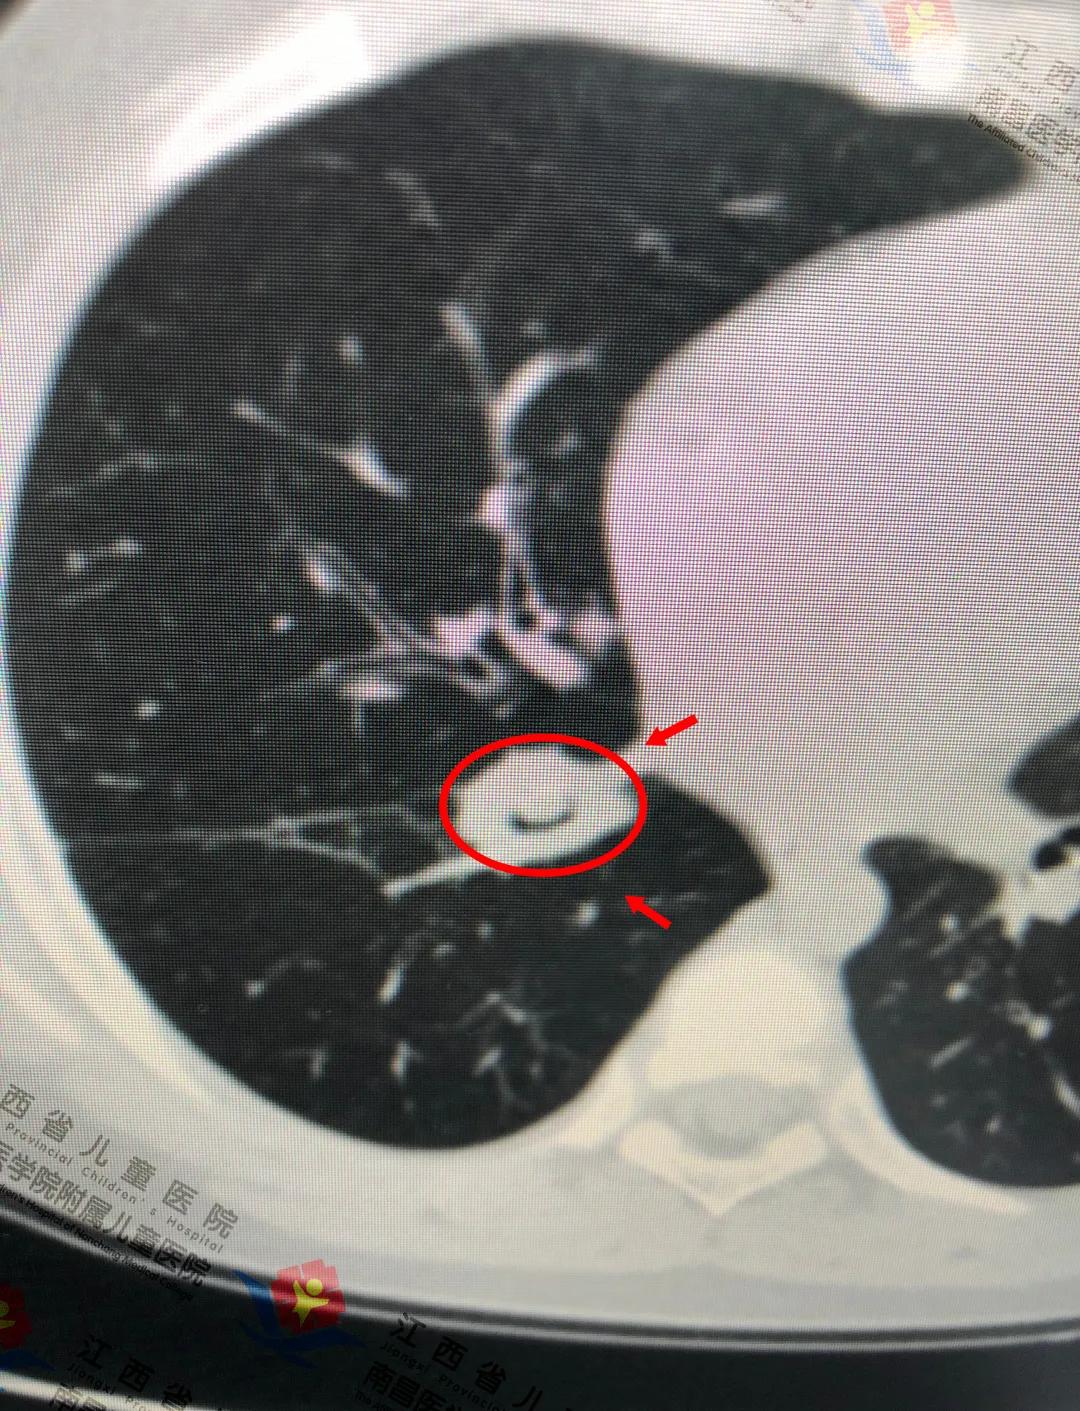

皓皓的肺部CT检查提示

右肺下叶支气管内可见异物、肺部感染